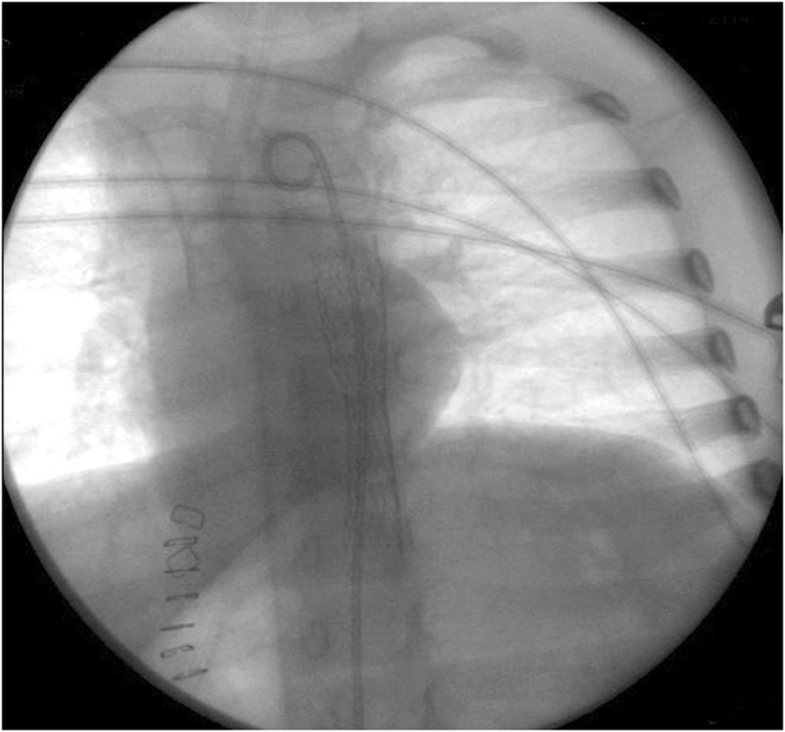

from coreem.net

Button Battery Ingestion Core EM